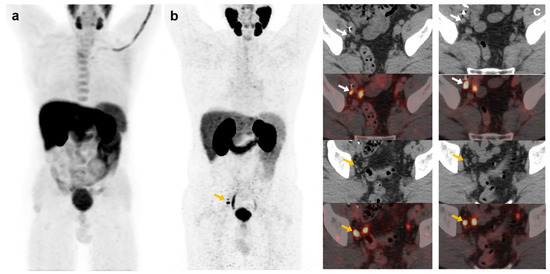

Figure 4.

70-year-old patient. Gleason 9 PCa, treated initially with RP and radiotherapy after his first BCR. Second BCR (PSA 0.7 ng/mL, PSAdt 5.6 months, PSAvel 0.05 ng/mL/month) with [18F]F-choline (a) and [18F]DCFPyL scans showing mediastinal lymph node tracer uptake (b) reported as inflammatory process. Follow-up was decided and PSA level continued increasing. A new [18F]DCFPyL scan (c) was performed 3 months later, showing an increase in size and metabolism of mediastinal lymph node with additional microfoci of radiotracer uptake in lung and bone, suspicious of metastases. An endobronchial ultrasound-guided lymph node biopsy confirmed prostatic origin of metastasis. ADT + Apalutamide was initiated (escalation).